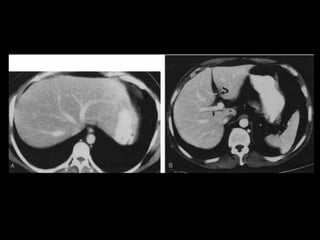

• TC: Tres fases

– Arterial (10 a 20 segundos)

– Fase venosa portal ( 30 segundos )

– Fase venosa hepática (60 segundos)

• TC Portografia: Metastases.